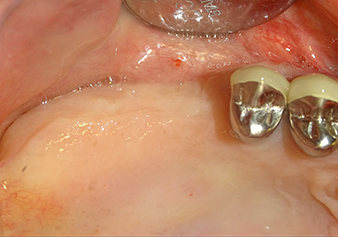

После промежуточного контроля (рис. 4) был проведен еще один этап подготовки (рис. 5). За тем, с помощью гидравлического инструмента Z35P мембрана была поднята в нужное положение (рис. 6 и 7). Далее, следовала дальнейшая пьезохирургическая подготовка ложа для имплантата, завершенная с помощью ротационного бора и лопаточной фрезы до диаметра имплантата 4,8 мм. Перед установкой имплантата под мембрану Шнейдера был введен аугментационный материал (размер частиц около 0,8-1,6 мм) (рис. 8).

Имплантация и протезирование

Для перемещения аугментационного материала в направлении верхнечелюстной пазухи атравматично, имплантат вводился очень медленно вручную (рис. 9). При этом мембрана еще раз выталкивалась в краниальном направлении. Через два месяца место операции зажило без раздражения. Через шесть месяцев рентгеновский контроль показал значительное увеличение помутнения, что свидетельствует об оссификации (рис. 10). Протезирование было проведено металлокерамической коронкой.